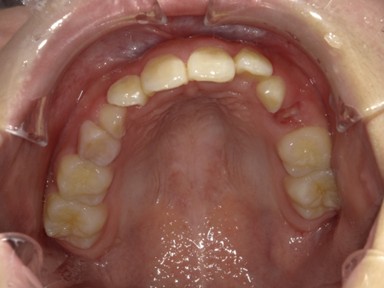

| 主訴 | 前歯が出ているので歯並びを良くしたい。 |

| 治療内容 | 使用装置:- マイオブレース(K1, K2, B1, K3) – 急速拡大装置 ・ワイヤー矯正:上顎前歯部(2-2)のみに2か月間使用 ・抜歯:なし |

| 治療費 | 550,000円(税込み) |

| 治療期間 | 2020年2月~2023年1月(永久歯列完成まで観察) |

| 治療回数 | 25回 |

| 想定されたリスク | 全額ワイヤー治療になる可能性とそれに伴う歯根吸収のリスクがありました。 |

かみ合わせが非常に深く、下顎の成長を妨げておりました。扁桃腺の肥大が一因として考えられたため切除の提案をしました。マイオブレースを中心に、短期間のワイヤー治療でかみ合わせも健康面も良好になったかと思います。